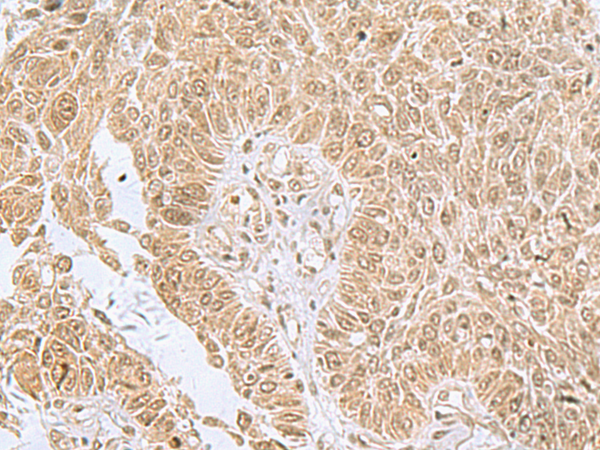

分类: 科研抗体货号: P00761别名: FLN29应用: WB,IHC反应种属: Human, Mouse